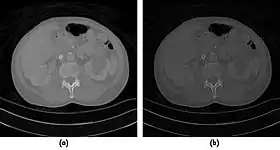

![]() Fig. 7.15.2: Effect of window width and level on CT image display: (a) Level = 50; Width = 200. (b) Level = 50; Width = 400. The image in (a) is displayed with greater contrast and appears noisier than that in (b). | ![]() Fig. 7.15.3: Effect of window width and level: (a) Level = -600; Width = 1700. (b) Level = -60; Width = 400. Image (a) displays the lung tissue more clearly, while image (b) can be used to highlight any pulmonary lesions. |

- Examples of image display manipulation are shown in the two figures above. In Figure 7.15.2, the same image of a slice through a patient's liver is displayed using a relatively narrow window (high contrast) and also with a wide window. The image with the narrower window appears noisier, but this is merely a reflection of the fact that the gray scale is spread over a narrow range of CT-numbers.

- Figure 7.15.3 illustrates the use of a relatively narrow window to highlight pathology in the lungs.